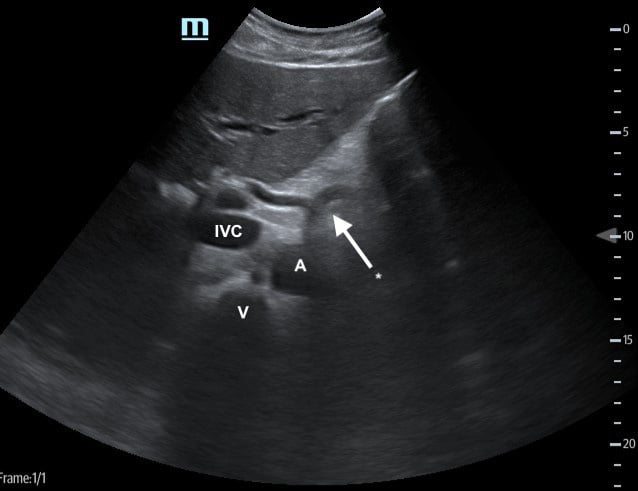

Periaortic region

- With the transducer in the subxyphoid region, transducer in the transverse plane, evaluate the periaortic region for large lymph nodes. (Figure 1, #2)

- Identify the arch of the vertebral body in the far field then the aorta just to the patient’s left.

- Identify the “seagull sign” of the celiac trunk and slide the transducer inferiorly to the bifurcation of the common iliac arteries.

- Normally, lymph nodes will be difficult to visualize because they are small and normally hypoechoic with a hyperechoic central hilum. As they enlarge, the architecture is distorted, and they develop a homogeneous echotexture. Attempt to image lymph nodes in 2 planes and measure the diameter.

Figure 3. Proximal aorta (A) with celiac trunk "seagull sign" (*) adjacent to the IVC and vertebral body (V)